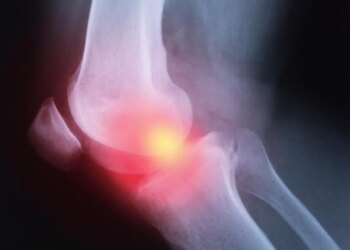

Read moreOsteoarthritis is a typical degenerative joint illness that primarily impacts the cartilage, the cushioning tissue between ...